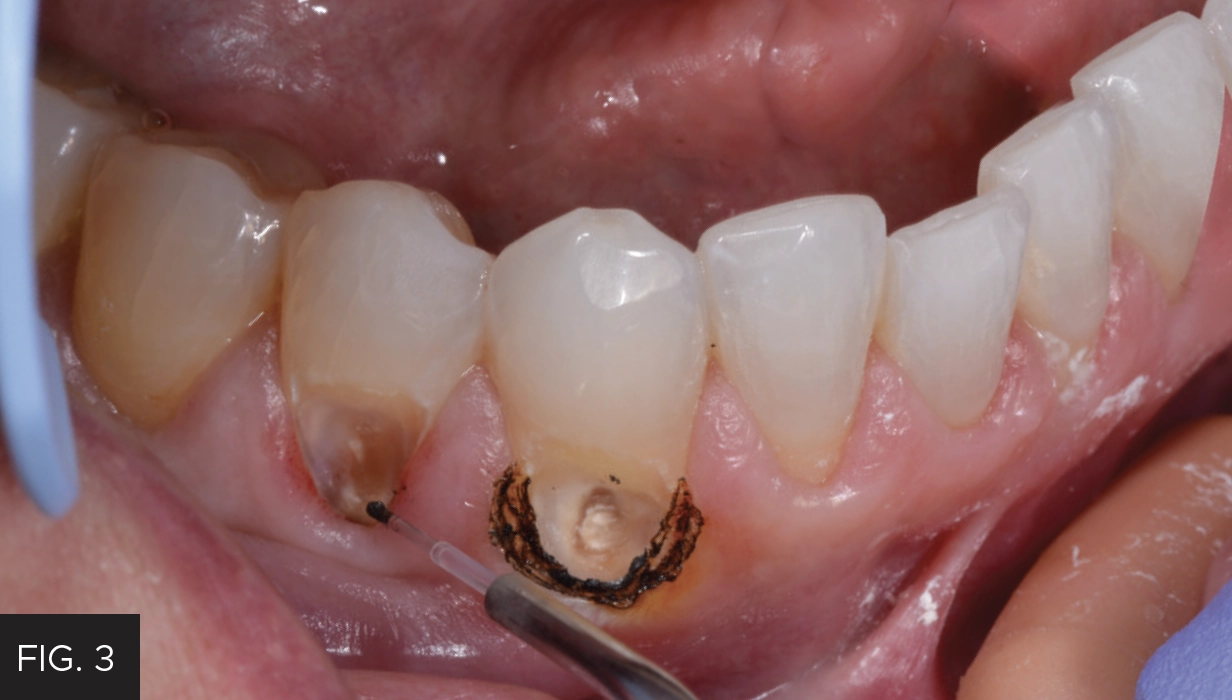

Initially, the decay was removed up to the free gingival margin. (FIG. 2) The retraction cord would not have retracted the tissue enough to complete the caries removal, so the laser procedure was utilized. The patient had already been anesthetized; however, additional anesthetic was placed in the buccal area adjacent to the prepared teeth. Prior to initiating laser treatment, a flexible periodontal probe (Hu-Friedy) was inserted into the periodontal pocket to determine where the level of the bone was positioned in order to prevent impingement of the biological width. The biologic width was determined to be approximately 2-3 mm, indicating adequate gingival tissue for a soft tissue laser procedure. In preparation for the procedure, the patient and all staff present had laser eye protection placed and a disposable, pre-bent tip was inserted into the Bluewave handpiece.